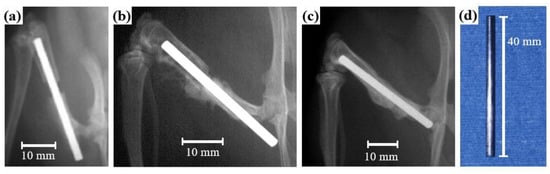

- Imai, K.; Hiromoto, S. In vivo evaluation of Zr-based bulk metallic glass alloy intramedullary nails in rat femora. J. Mater. Sci. Mater. Med. 2014, 25, 759–768. [Google Scholar] [CrossRef] [PubMed]

- Imai, K.; Hiromoto, S. In vivo evaluation of bulk metallic glasses for osteosynthesis devices. Materials 2016, 9, 676. [Google Scholar] [CrossRef] [PubMed]

- Kokubun, R.; Wang, W.; Zhu, S.; Xie, G.; Ichinose, S.; Itoh, S.; Takakuda, K. In vivo evaluation of a Ti-based bulk metallic glass alloy bar. Bio-Med. Mater. Eng. 2015, 26, 9–17. [Google Scholar] [CrossRef]

- Lin, C.H.; Chen, C.H.; Huang, Y.S.; Huang, C.H.; Huang, J.C.; Jang, J.S.C.; Lin, Y.S. In-vivo investigations and cytotoxicity tests on Ti/Zr-based metallic glasses with various Cu contents. Mater. Sci. Eng. C 2017, 77, 308–317. [Google Scholar] [CrossRef]